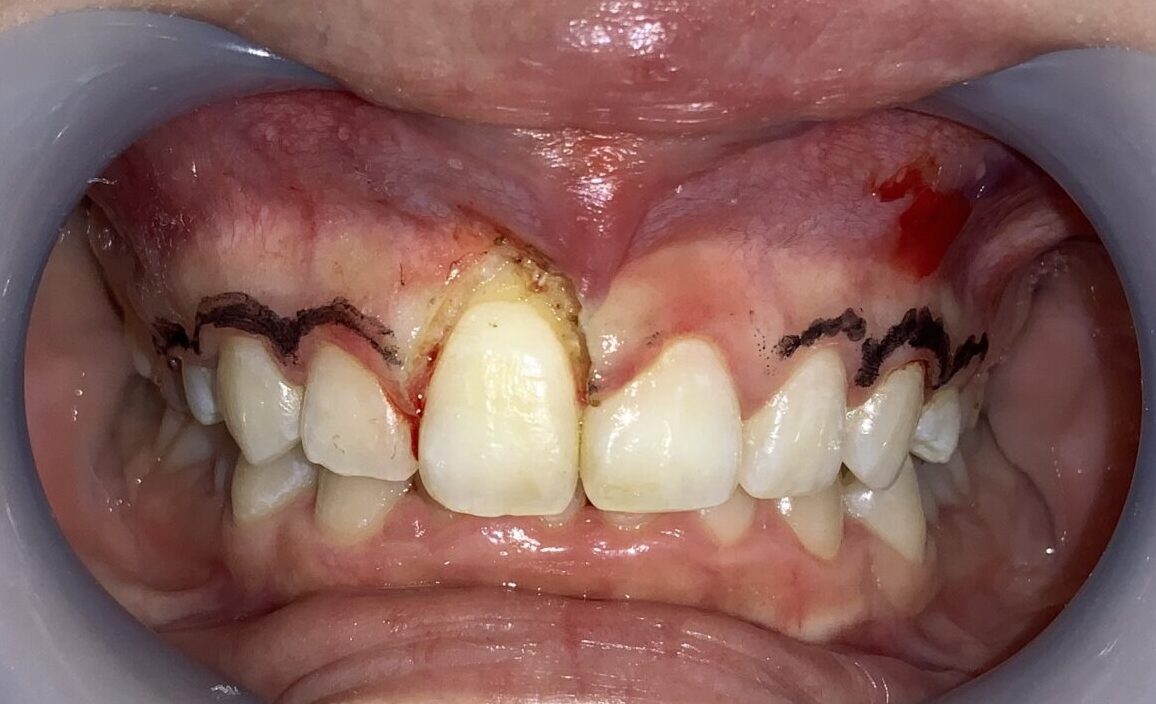

手術前の状態から見て参ります。

歯ぐきが被っており、歯が小さく、左右差があります。歯ぐきが被っている影響で歯ブラシの清掃が届かないので、プラークの堆積や歯ぐきの発赤も認められます。

前歯から順番に検査をして参ります。

歯ぐきの被っている量は相当あります。また、歯ぐきが分厚くて、繊維状に変性をしているようです。しっかり整えましょう。